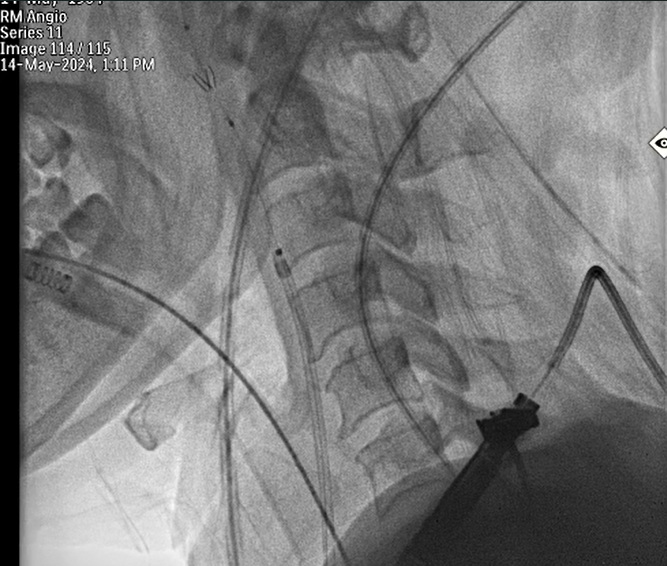

Cerebral Protection was done with one filter and two peripheral balloons

Transeptal Puncture was done and was later exchanged with 8.5fr deflectable Agilis sheath

Bilateral Radial and Femoral artery access taken along with Right Femoral vein under Ultrasound guidanceCarotid filter was placed in Right carotid artery through Right femoral arteryTwo Peripheral balloons were kept in left common carotid and left subclavian through left femoral and radial artery routeTranseptal puncture through right femoral vein was done and was later exchanged with 8.5fr deflectable Agilis sheathThrough Agilis sheath valve orifices was crossed with 0.032 Terumo wireUpper Orifice was dilated with 12x140mm peripheral balloonCentral Orifice was dilated with 5x60mm peripheral balloonLower Orifice was dilated with 10x140mm peripheral balloonPost Procedure Good movement of both leaflets , still upper leaflet movement was not satisfactory.6fr Decapolar mapping catheter was used for pecking the upper leaflet and later again it was dilated with 12x140mm peripheral balloon.Movement of both leaflets were good